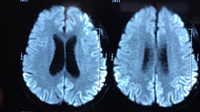

RNM cranioencefálica: o sinal pulvinar (um termo que se refere à hiperintensidade pulvinar bilateral) em um paciente com doença de Creutzfeldt-Jakob em imagens ponderadas por difusão

Do acervo pessoal de Leo H. Wang; usado com permissão

RNM cranioencefálica: fitas corticais (hiperintensidade nos giros corticais) em um paciente com doença de Creutzfeldt-Jakob em imagens ponderadas por difusão